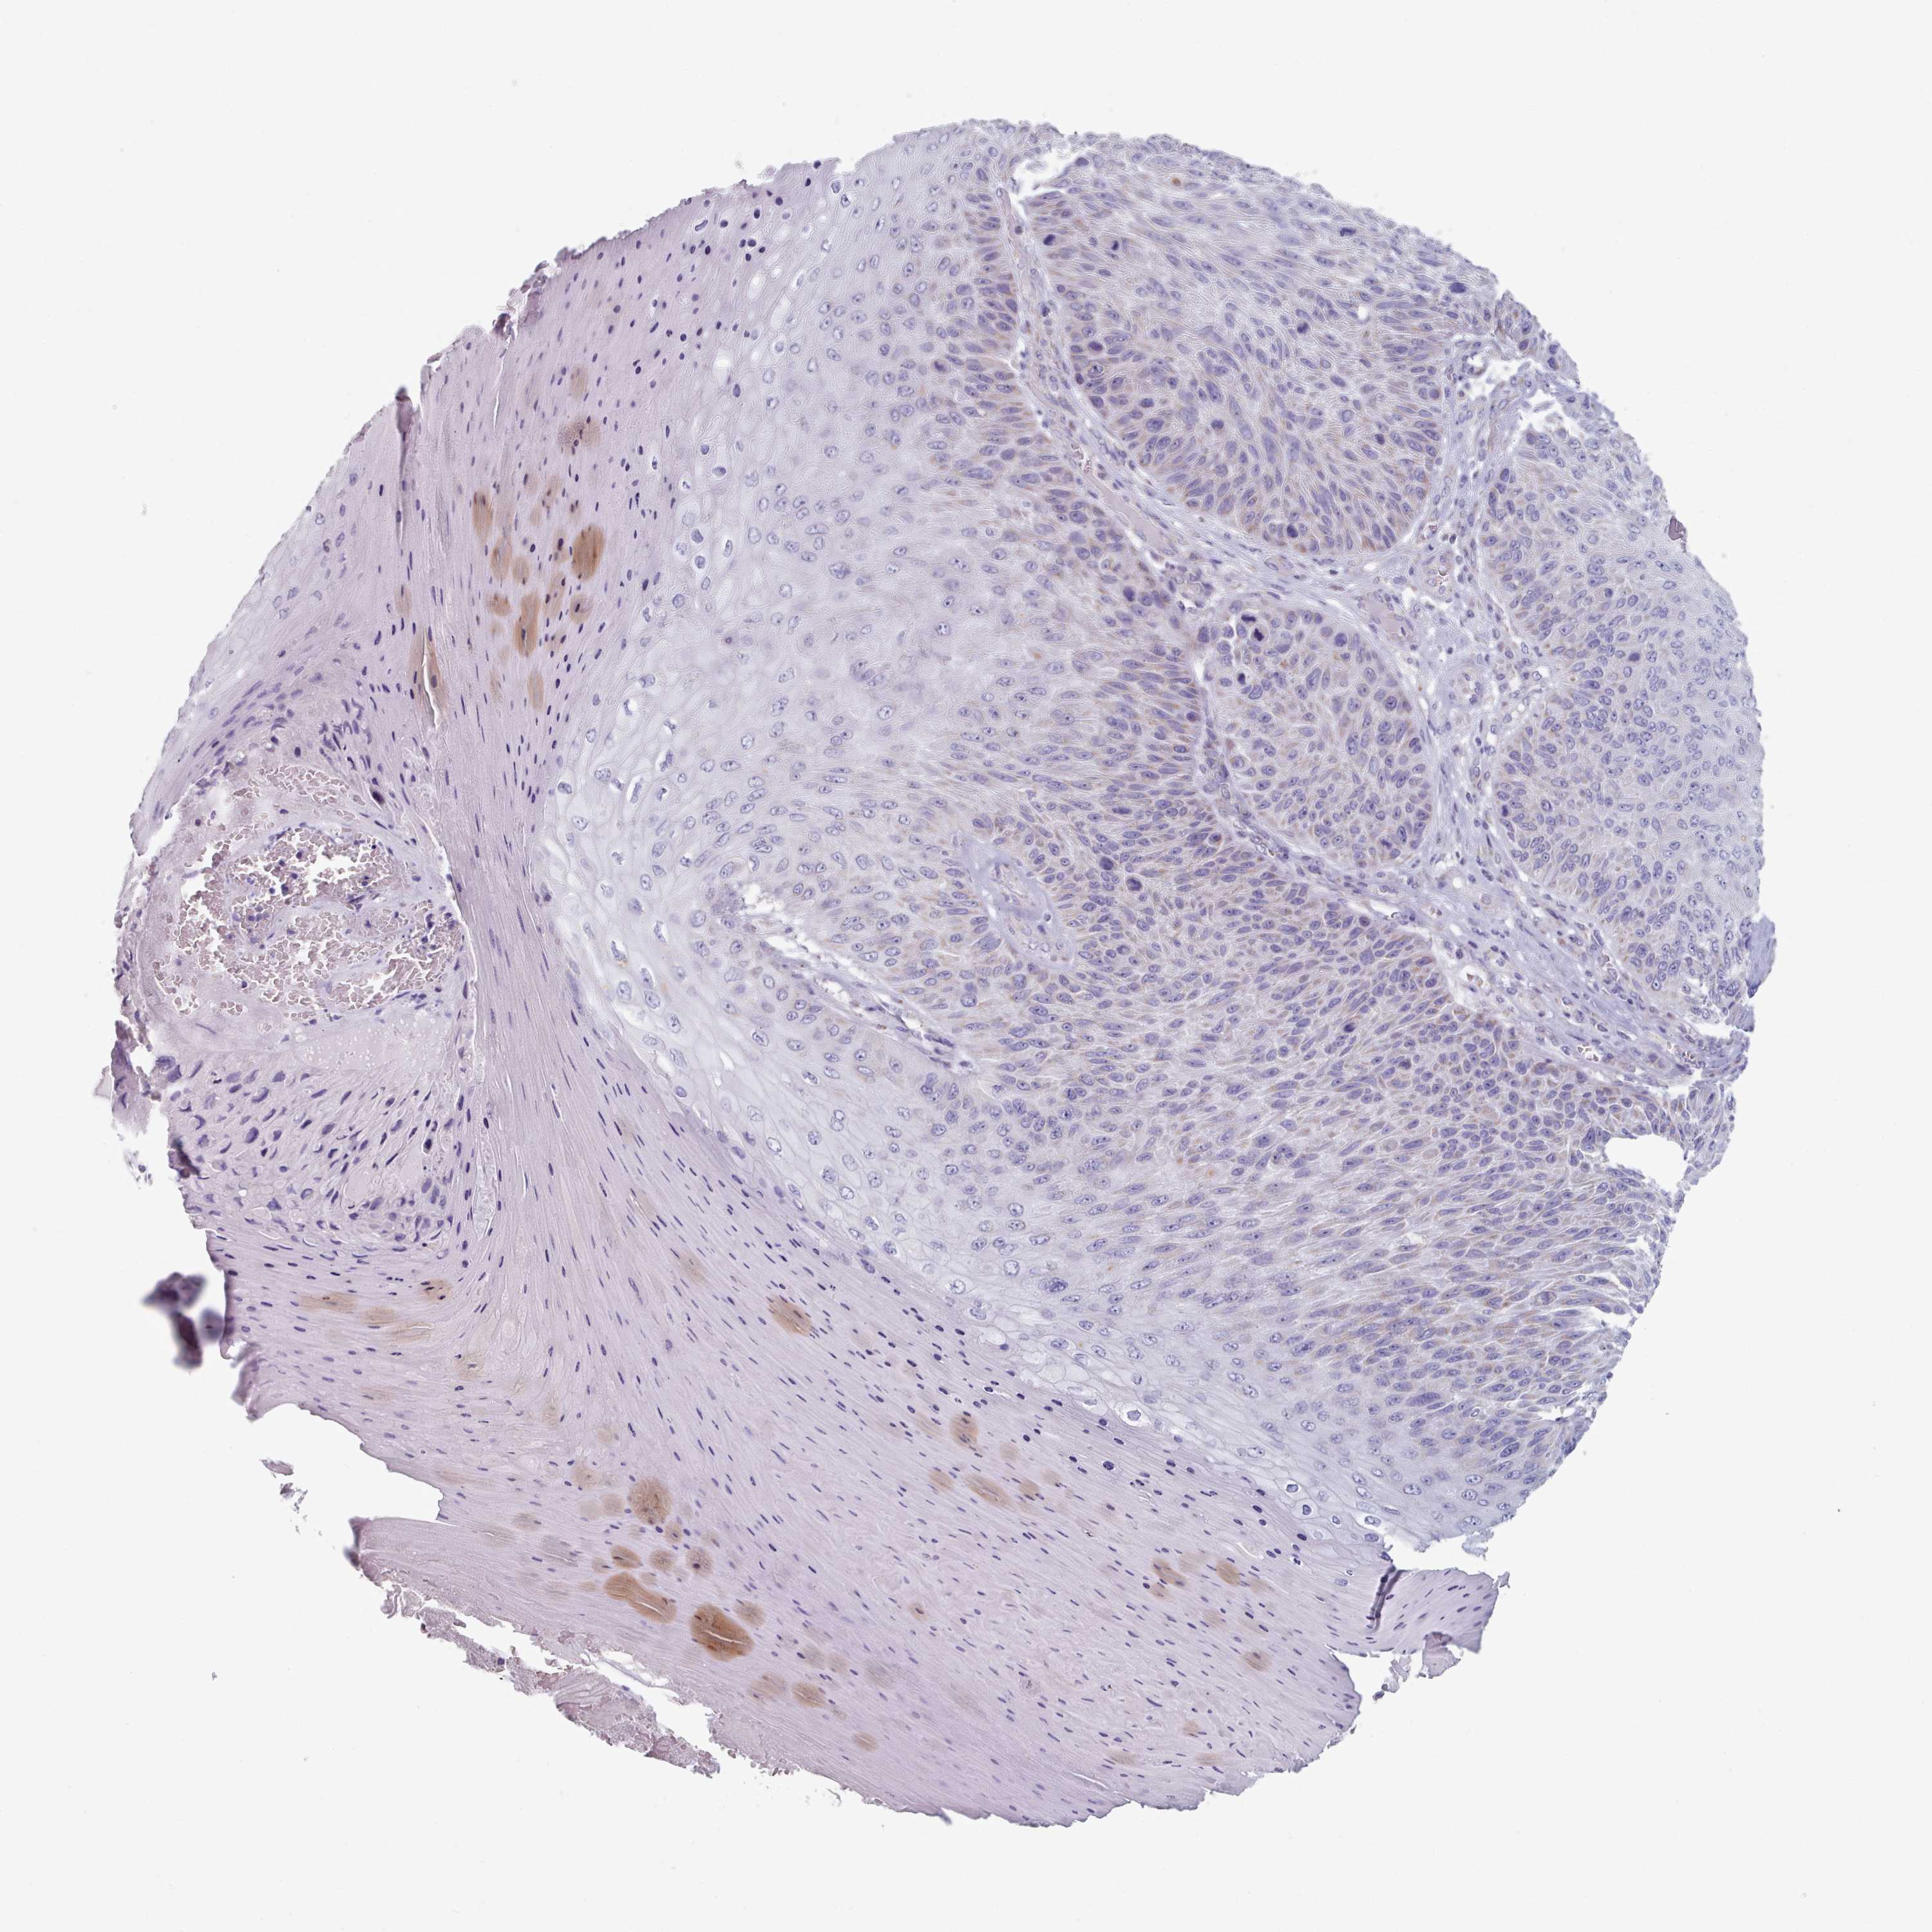

Basal cell and squamous cell cancer

SKIN CANCER - Protein expressioni

A mouse-over function shows sample information and annotation data. Click on an image to view it in a full screen mode. Samples can be filtered based on level of antibody staining by selecting one or several of the following categories: high, medium, low and not detected. The assay and annotation is described here.

Antibody stainingi

Antibody staining in the annotated cell types in the current human tissue is reported as not detected, low, medium, or high, based on conventional immunohistochemistry profiling in selected tissues. This score is based on the combination of the staining intensity and fraction of stained cells.

Each image is clickable and will lead to virtual microscopy that enables deeper exploration of all samples and also displays staining intensity scores, fraction scores and subcellular localization as well as patient and tissue information for each sample.

Antibody HPA049552

Antibody HPA072442

Staining

High

Medium

Low

Not detected

Intensity

Strong

Moderate

Weak

Negative

Quantity

>75%

75%-25%

<25%

None

Location

Nuclear

Cytoplasmic/membranous

Cytoplasmic/membranous,nuclear

Basal cell carcinoma

Squamous cell carcinoma, NOS

Squamous cell carcinoma, metastatic, NOS